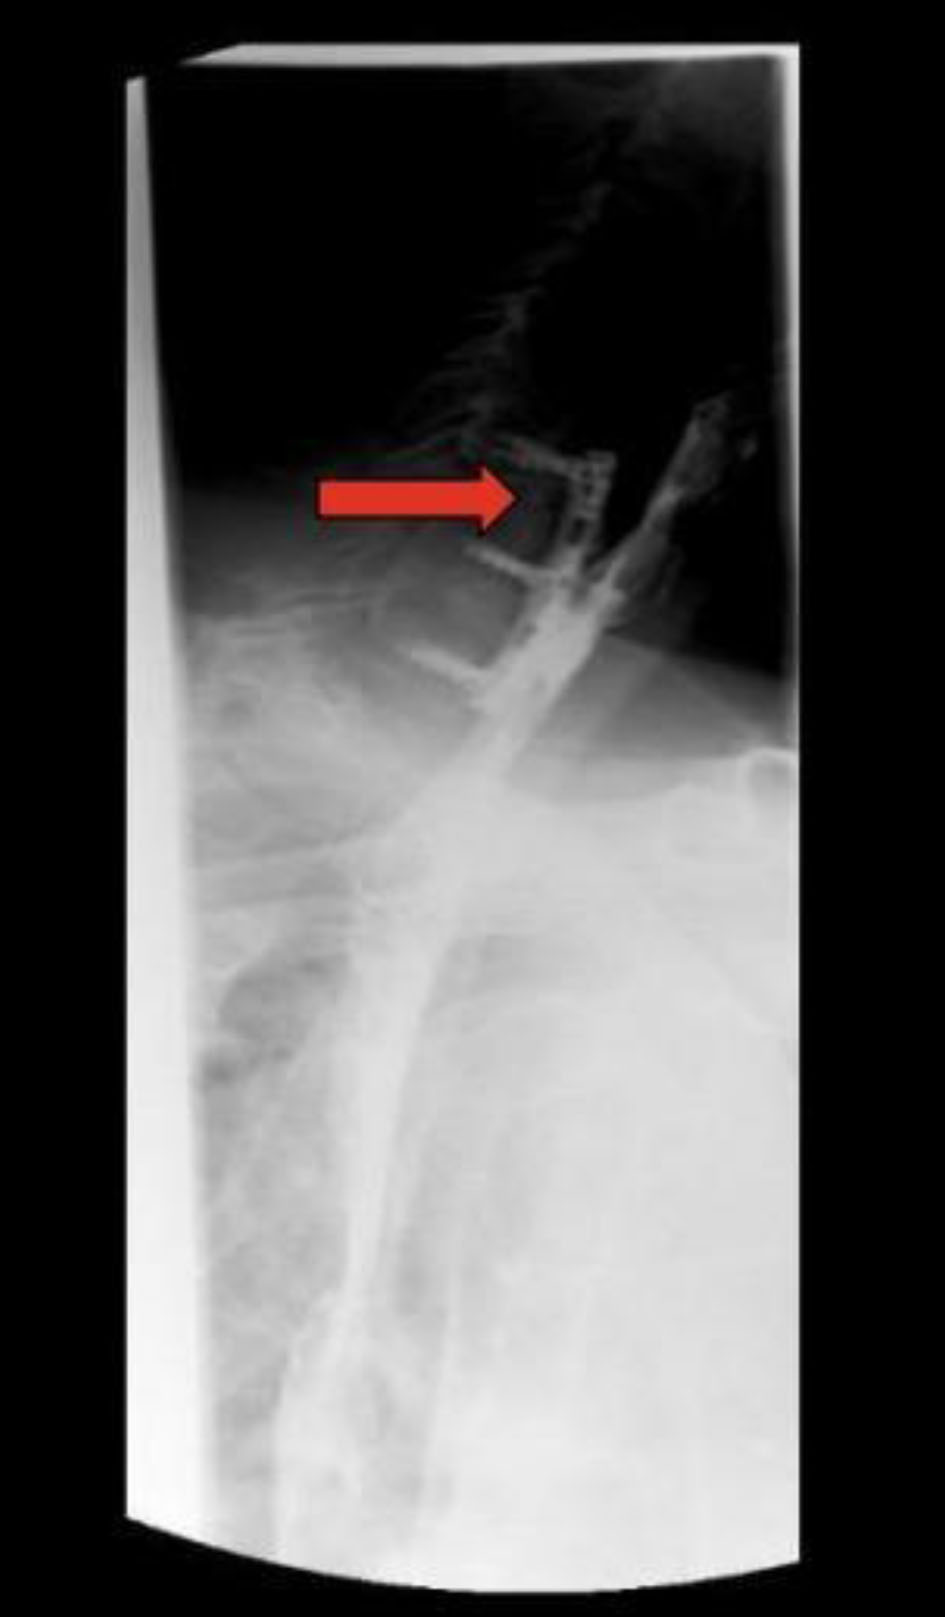

After 6 more months of persistent dysphagia and weight loss without a diagnosis, the patient presented to our network for further workup and treatment recommendations. CT of the neck 12 months postoperatively showed anterior cervical plate in adequate position with air between the plate and esophagus (Fig. 2). An upper endoscopy was performed at 12 months postoperatively, which showed fistulization between the esophagus and the metal hardware in the cervical spine. An esophagram was also performed, which demonstrated no obstruction but decreased peristalsis of the lower esophagus and lateral rightward deviation of the left upper cervical esophagus with minimal mucosal irregularities. Esophagram also showed involvement of the posterior wall of the cervical esophagus overlying the anterior plate and screws without evidence of leak or fistula (Fig. 3).

![]() Click for large image | Figure 3. Esophagram at 12 months. Red arrow indicates defect. The image shows contiguity between the lumen of the esophagus and the cervical hardware based on the transit of the oral contrast, consistent with a posterior esophageal wall perforation contained by the cervical hardware without extravasation. |